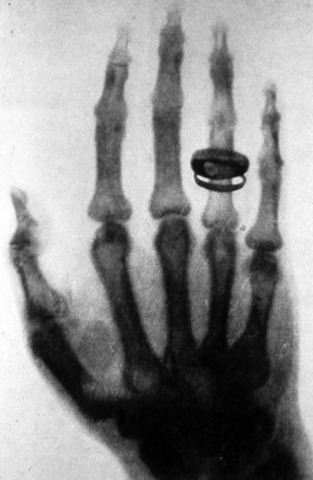

Wilhelm Roentgen discovers x-ray, and then he conform the functionality of the x-ray by tasting it out on his wifes hand.